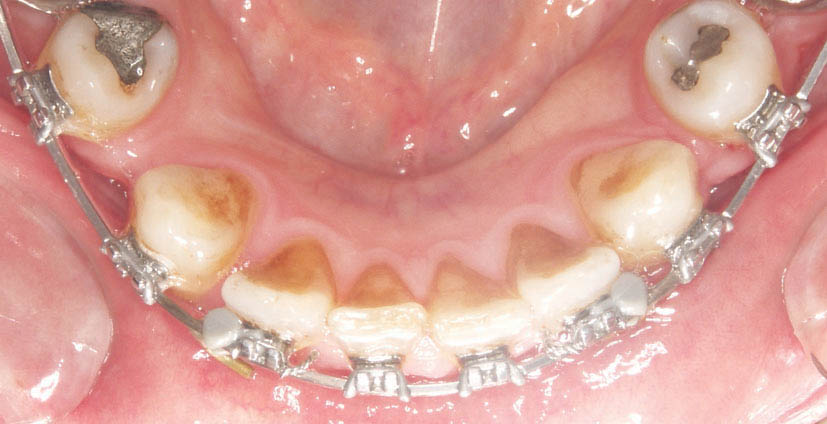

روتیشنوج (شکل 169-1) عمدتاً در قدامیهای پایین كاربرد دارد. بعد از برطرف شدن چرخش انسیزورهای پائین با سیم 0.012 سوپرالاستیک و سیم 0.016 حرارتی، موقع over treatment در چرخش آنها است. برای این کار از روتیشنوج استفاده میکنیم.

در شکل 170-1 میبینید که نیمه دیستالی لترالهای پایین به سمت لبیال چرخش دارد. ابتدا سیم 0.016 حرارتی گذاشته تا دندانها مرتب شوند، بعد آن را خارج میکنیم و روتیشنوج را روی انسیزورهایی که در قدیم چرخش داشتهاند (در این مورد دیستال لترالها میباشد) میگذاریم. دو سوراخ ریز روی آنها وجود دارد که باید درگیر دو بالچه مزیالی یا دیستالی کنید.

شکل 170-1: دیستال لترالهای پائین در ابتدای درمان به سمت لبیال هستند.

اگر در ابتدای درمان دیواره دیستالی به سمت لبیال چرخش داشته باشد باید روتیشنوج را بر روی بالچههای دیستالی بگذارید. اگر دیواره مزیالی به سمت لبیال چرخش داشته باید روتیشنوج را بر روی بالچههای مزیالی بگذارید، در این بیمار روی بالچههای دیستالی میگذاریم (شکل 171-1). بعد سیم 0.019x0.025 حرارتی را قرار دهید. شما نمیتوانید oring روی این براکت بیندازید، لذا وایر لیگاچور کنید. این روتیشنوج بایستی تا انتهای درمان بماند و همیشه روی براکت آن وایر لیگاچور شود (شکل 172-1). فقط در 4-2 هفته آخر که مرحله استقرار (فاز Settling) است باید آن را در بیاوریم تا قبل از خارج کردن براکتها، تمام دندانها مرتب باشند.

شکل 171-1: بعد از مرتب شدن انسیزور در شکل 166-1، روتیشن وج روی نیمه دیستالی میگذاریم، بعد آرچ وایر 0.019x0.025 حرارتی را روی آن قرار میدهیم تا باعث لینگوالی شدن بیشتر دیستال آن بشود.